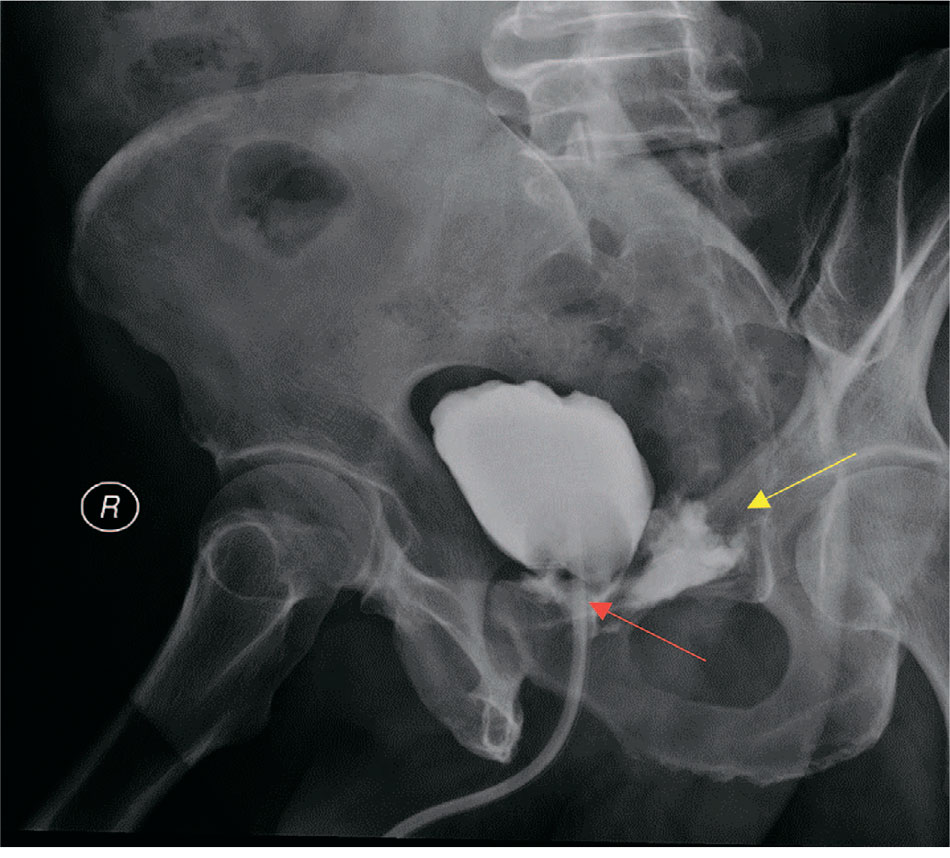

У четырех пациентов, прошедших РПЭ с использованием лапароскопического и робот-ассистированного доступа в процессе изучения и освоения данных методов, была обнаружена несостоятельность анастомоза между мочевым пузырем и уретрой, подтвержденная на цистографии (рис. 5, табл. 3).

Рис. 5. Экстравазация контрастного вещества (указан желтой стрелкой) – признак несостоятельности цистоуретроанастомоза (указан красной стрелкой)

Fig. 5. Extravasation of the contrast agent (indicated by the yellow arrow) is a sign of the failure of cystourethroanastomosis (indicated by the red arrow)

В описанных эпизодах потребовалась длительная (до 60 суток) катетеризация мочевого пузыря с целью обеспечения формирования цистоуретроанастомоза (ЦУА), что в итоге привело к полной утрате способности удержания мочи.